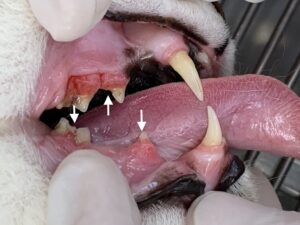

口の中を視診すると歯の表面に歯肉が覆いかぶさっている部分が見られます。これは歯の吸収病巣という病気の典型的な特徴で、歯の表面が溶けてその部分に炎症を起こした歯肉が盛り上がって覆いかぶさっている状態です。他に血液検査や全身の画像検査では大きな異常が見られない場合、口の痛みによって食欲が落ちていることが疑われます。